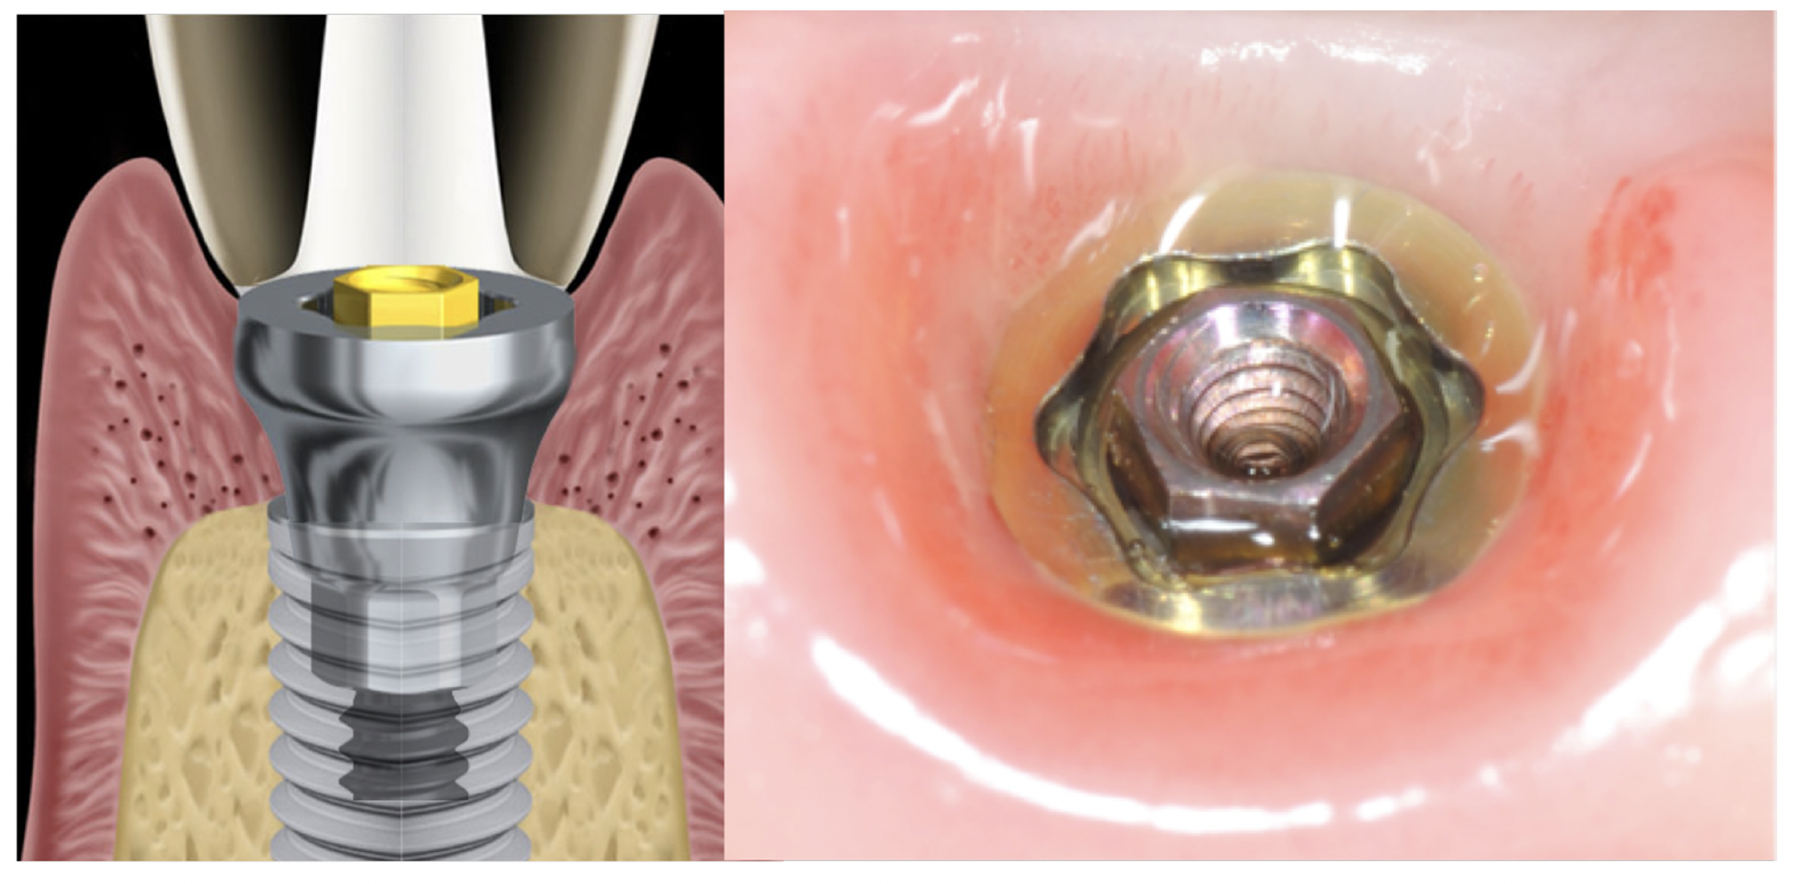

Tissue integration also depends on the surface properties of the materials in contact with peri-implant tissues, such as the surface energy and the decontamination and sterilization of the surfaces. Customized Computer-Aided Design/Computer-Aided Manufacturing (CAD/CAM) titanium and zirconia abutments may be fabricated using multiple technical procedures, all of which inevitably contaminate the surfaces of the materials, thus potentially compromising soft tissue integration and adherence.32 In vitro results have suggested that the decontamination of abutment surfaces is important for early fibroblast adherence and may improve the biological integration of peri-implant soft tissues.29 Ideally, abutments should have a surface that is completely decontaminated and sterilized, so as to allow for tight soft tissue adherence and integration in the subcritical and critical zones to support peri-implant tissues as well as create an effective soft-tissue seal/defense area against bacterial microorganisms. To achieve the best clinical performance in terms of soft tissue adherence, stock final abutments that are completely decontaminated and sterilized, with surface chemistry that boosts their biological response, should be the first choice (Figure 3 and Figure 4). These abutments are available in multiple heights, which should be selected based on the implant site, the vertical soft tissue thickness, and the esthetic expectations.

Finally, once the proper 3D position of the implants has been identified, the abutment placement protocol to be used should be evaluated. The "one abutment/one time" approach4,6,8,17 allows soft tissues to adhere firmly onto the surface of titanium abutments, thereby improving soft tissue response and bone stability (Figure 4 and Figure 7 through Figure 14 ). This approach avoids multiple connections and disconnections at the bone interface and favors undisturbed bone and soft tissue healing.4-7

Fig. 4